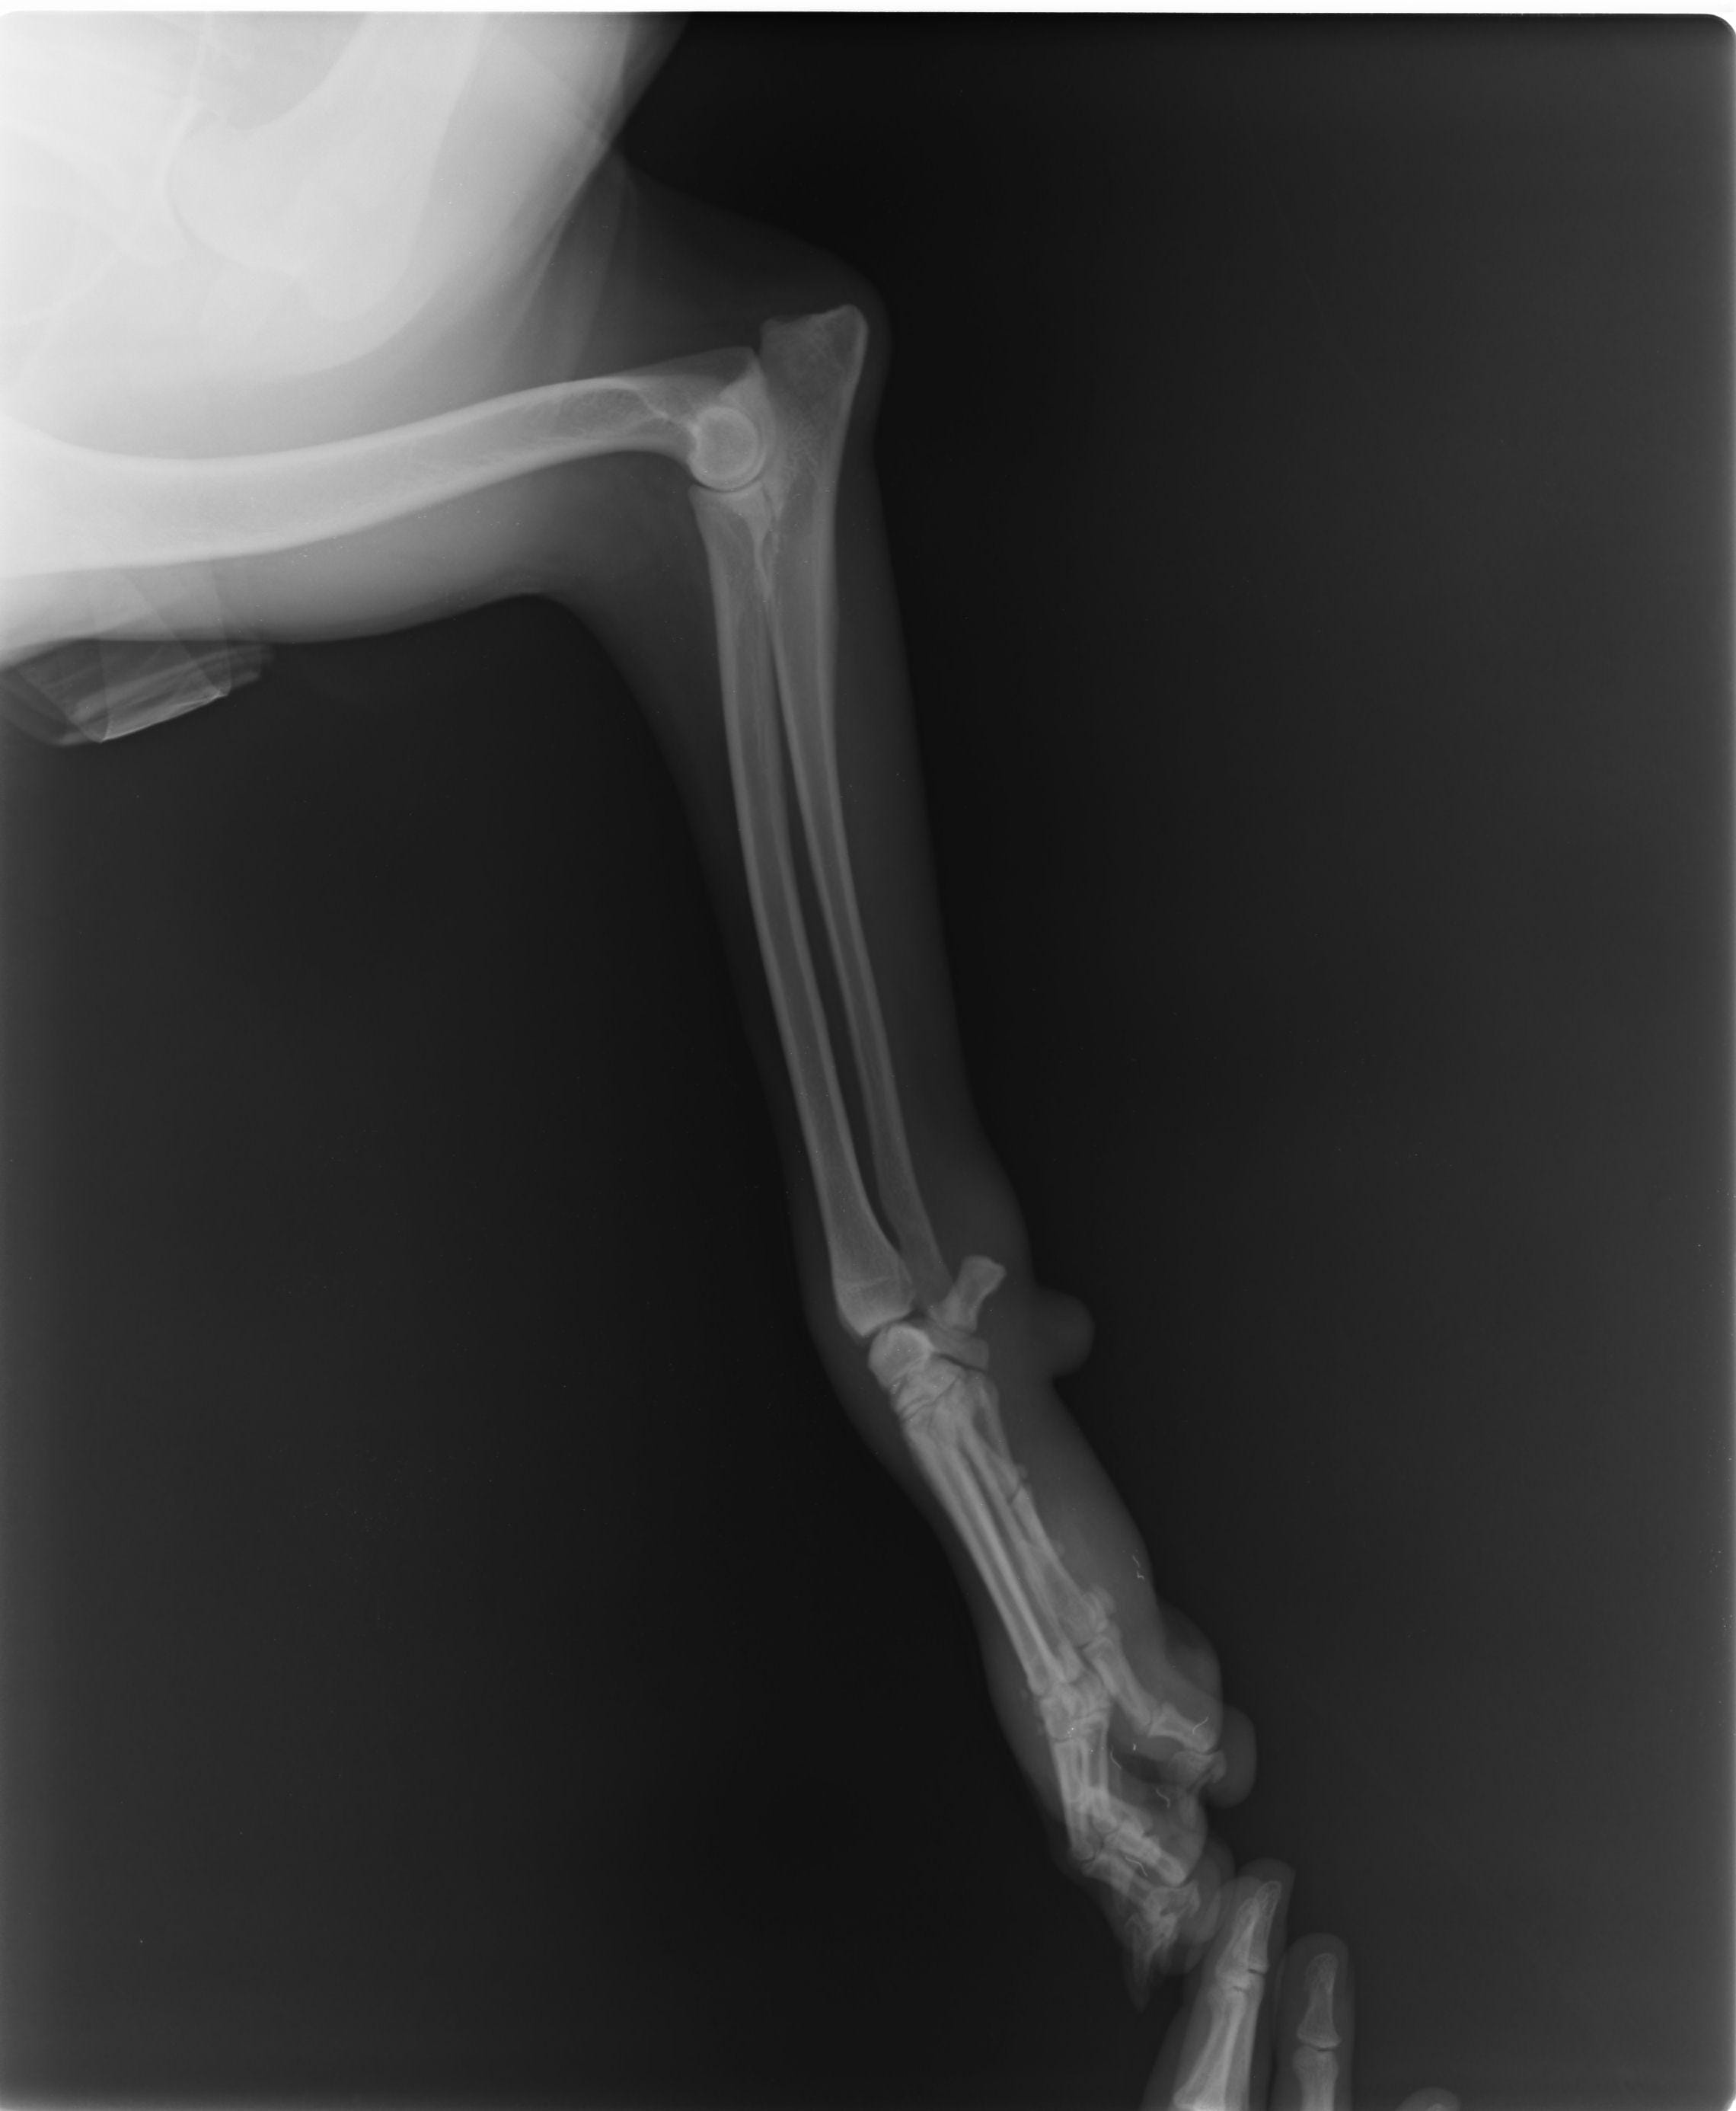

Hi. I live in lebanon and my belgian malinois has hurt her right wrist. I took her to the the 1st vet and he said that the swelling will go away and there was no fracture. I wasnt convinced so i took her to a 2nd vet who said that that there is fracture and he put a cast on her leg. Without a cast she shows signs of carpal hyperextension, but the vet said it isnt the case. From the xray images does it show a fracture, and if it does does it produce symptons of carpal hyperextension? Thanks a lot

It does look like there is fracture on the last phalang of what i assume is the right wrist (it's not indicated on the xray so can't know 100%), i cannot tell if it is causing symptoms of hyperextension from the xray but it was in my opinion the right decision to cast it for it to heal better.